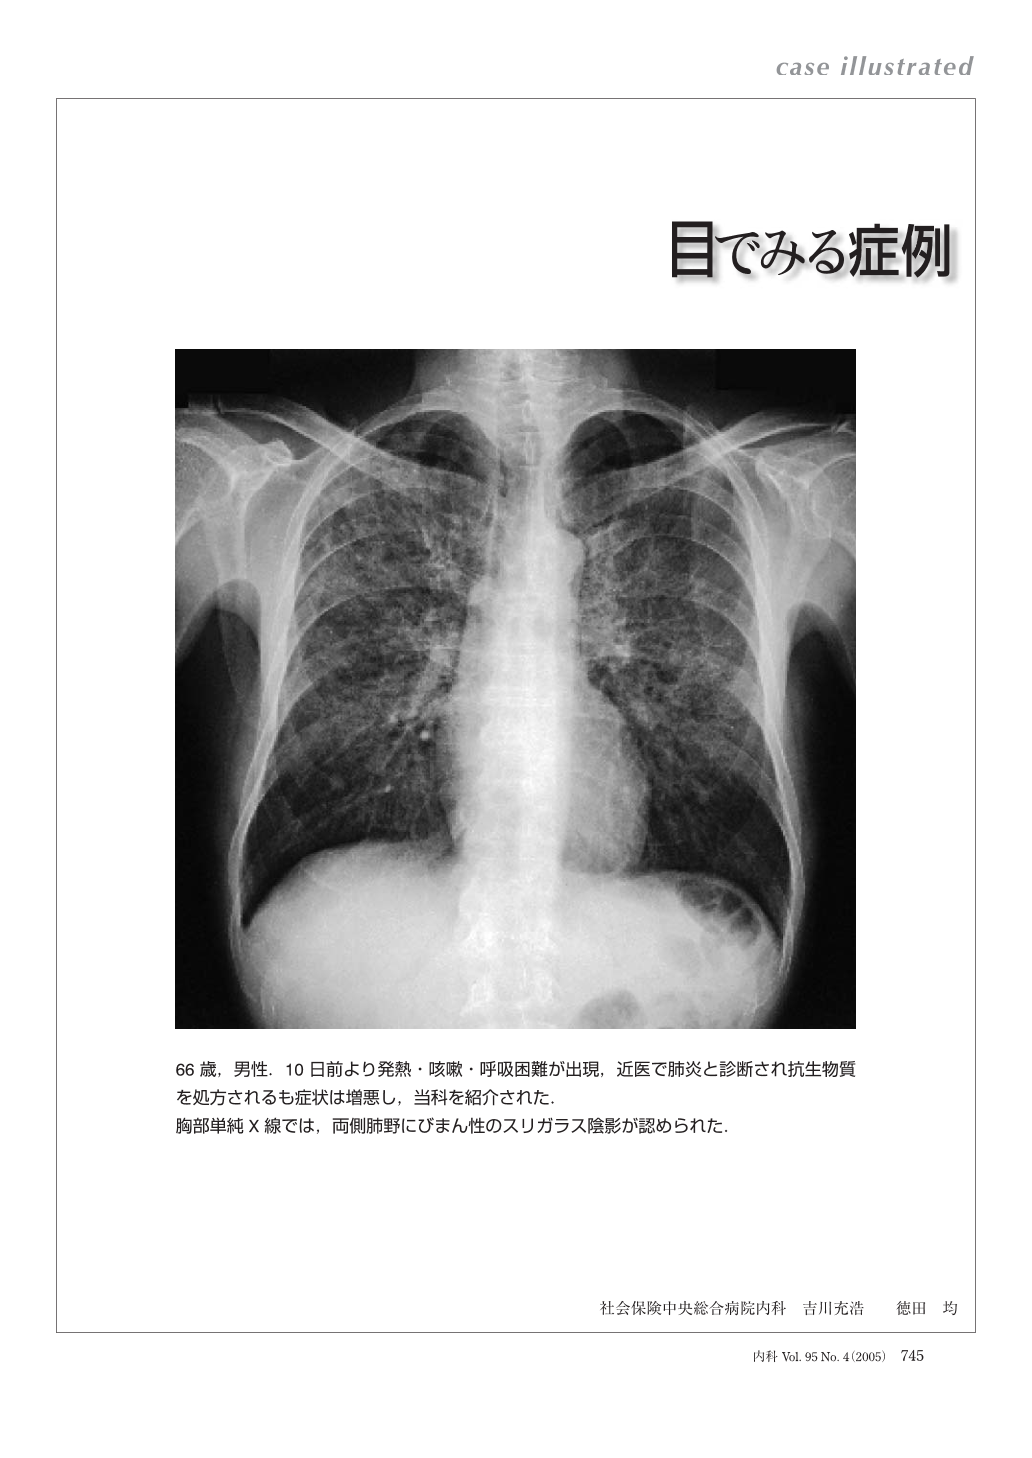

症例に学ぶ新生児X線診断。新版胸部単純X線診断: 画像の成り立ちと読影の進め方 | 林 邦昭。目でみる症例 ニューモシスチス肺炎 (臨床雑誌内科 95巻4号。